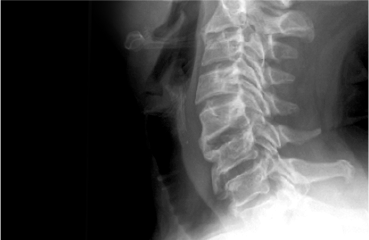

척추체와 척추관 사이에서 척추의 정렬 및 안정화, 운동성을 유지하기 위해

존재하는 구조물을

후종인대라고 합니다. 다양한 원인에 의해 후종인대가 뼈처럼

단단하게 굳어지는 골화를 일으켜 척추관을 압박함으로써 신경장애가 나타나는

질환을 후종인대 골화증이라고 합니다.

목 부분인 경추에서 주로 발생하며,

경우에 따라 가슴 쪽 흉추에서도 드물게 발생합니다.